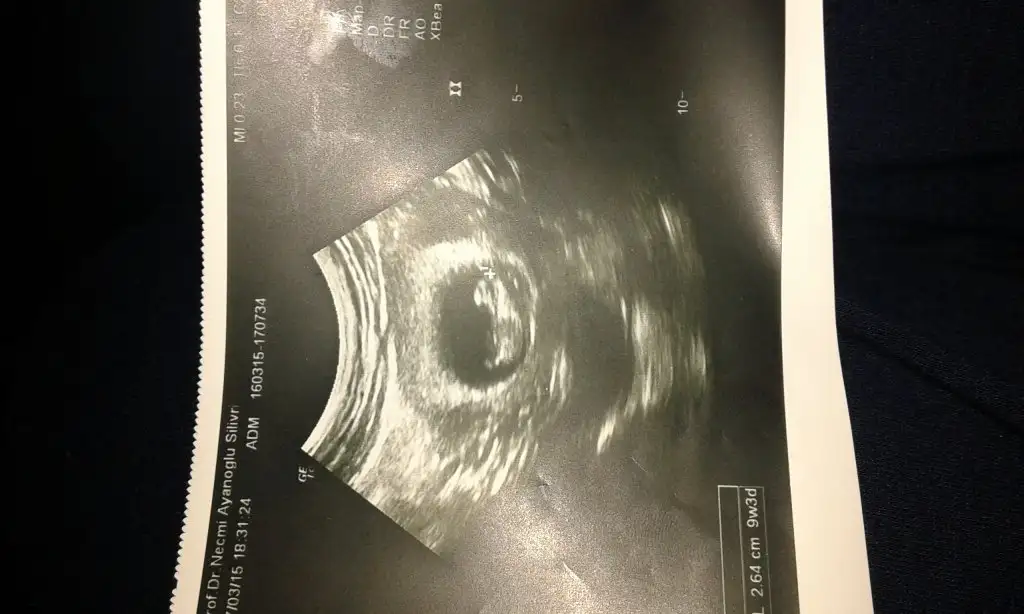

Kızlar 12.haftamdayim sizce cinsiyeti ne

Eklentiler

• IMAG6293.webp

IMAG6293.webp

21,8 KB · Görüntüleme: 169